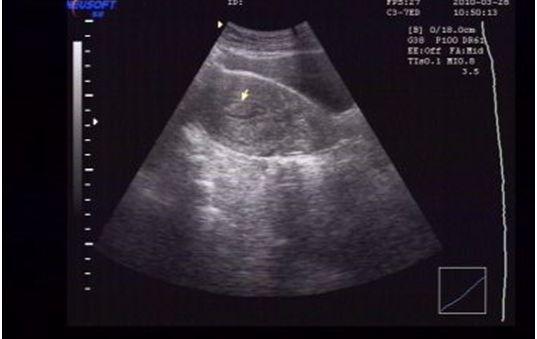

子宫内膜变化是卵巢的内分泌即雌、孕激素作用而出现,与卵泡发育的排卵过程一致。排卵前,卵巢以分泌雌激素为主,使内膜仅发生增殖性变化。在排卵后期在雌孕激素联合作用下使子宫内膜发生特殊的分泌性变化,子宫内膜的声像图也有相应的改变。增殖期内膜多呈线状回声,分泌期和月经期由于内膜水肿,腺体分泌,血管增殖,则表现为典型的“三线”征,即外层为高回声的基底层,内层为低回声的内膜功能层,中央的条状高回声为宫腔粘液,(或两层内膜结合线)。

生育期妇女的双层内膜厚度约为5-12mm,分泌期最厚度可达14mm,绝经期后妇女内膜变薄,小于6mm。